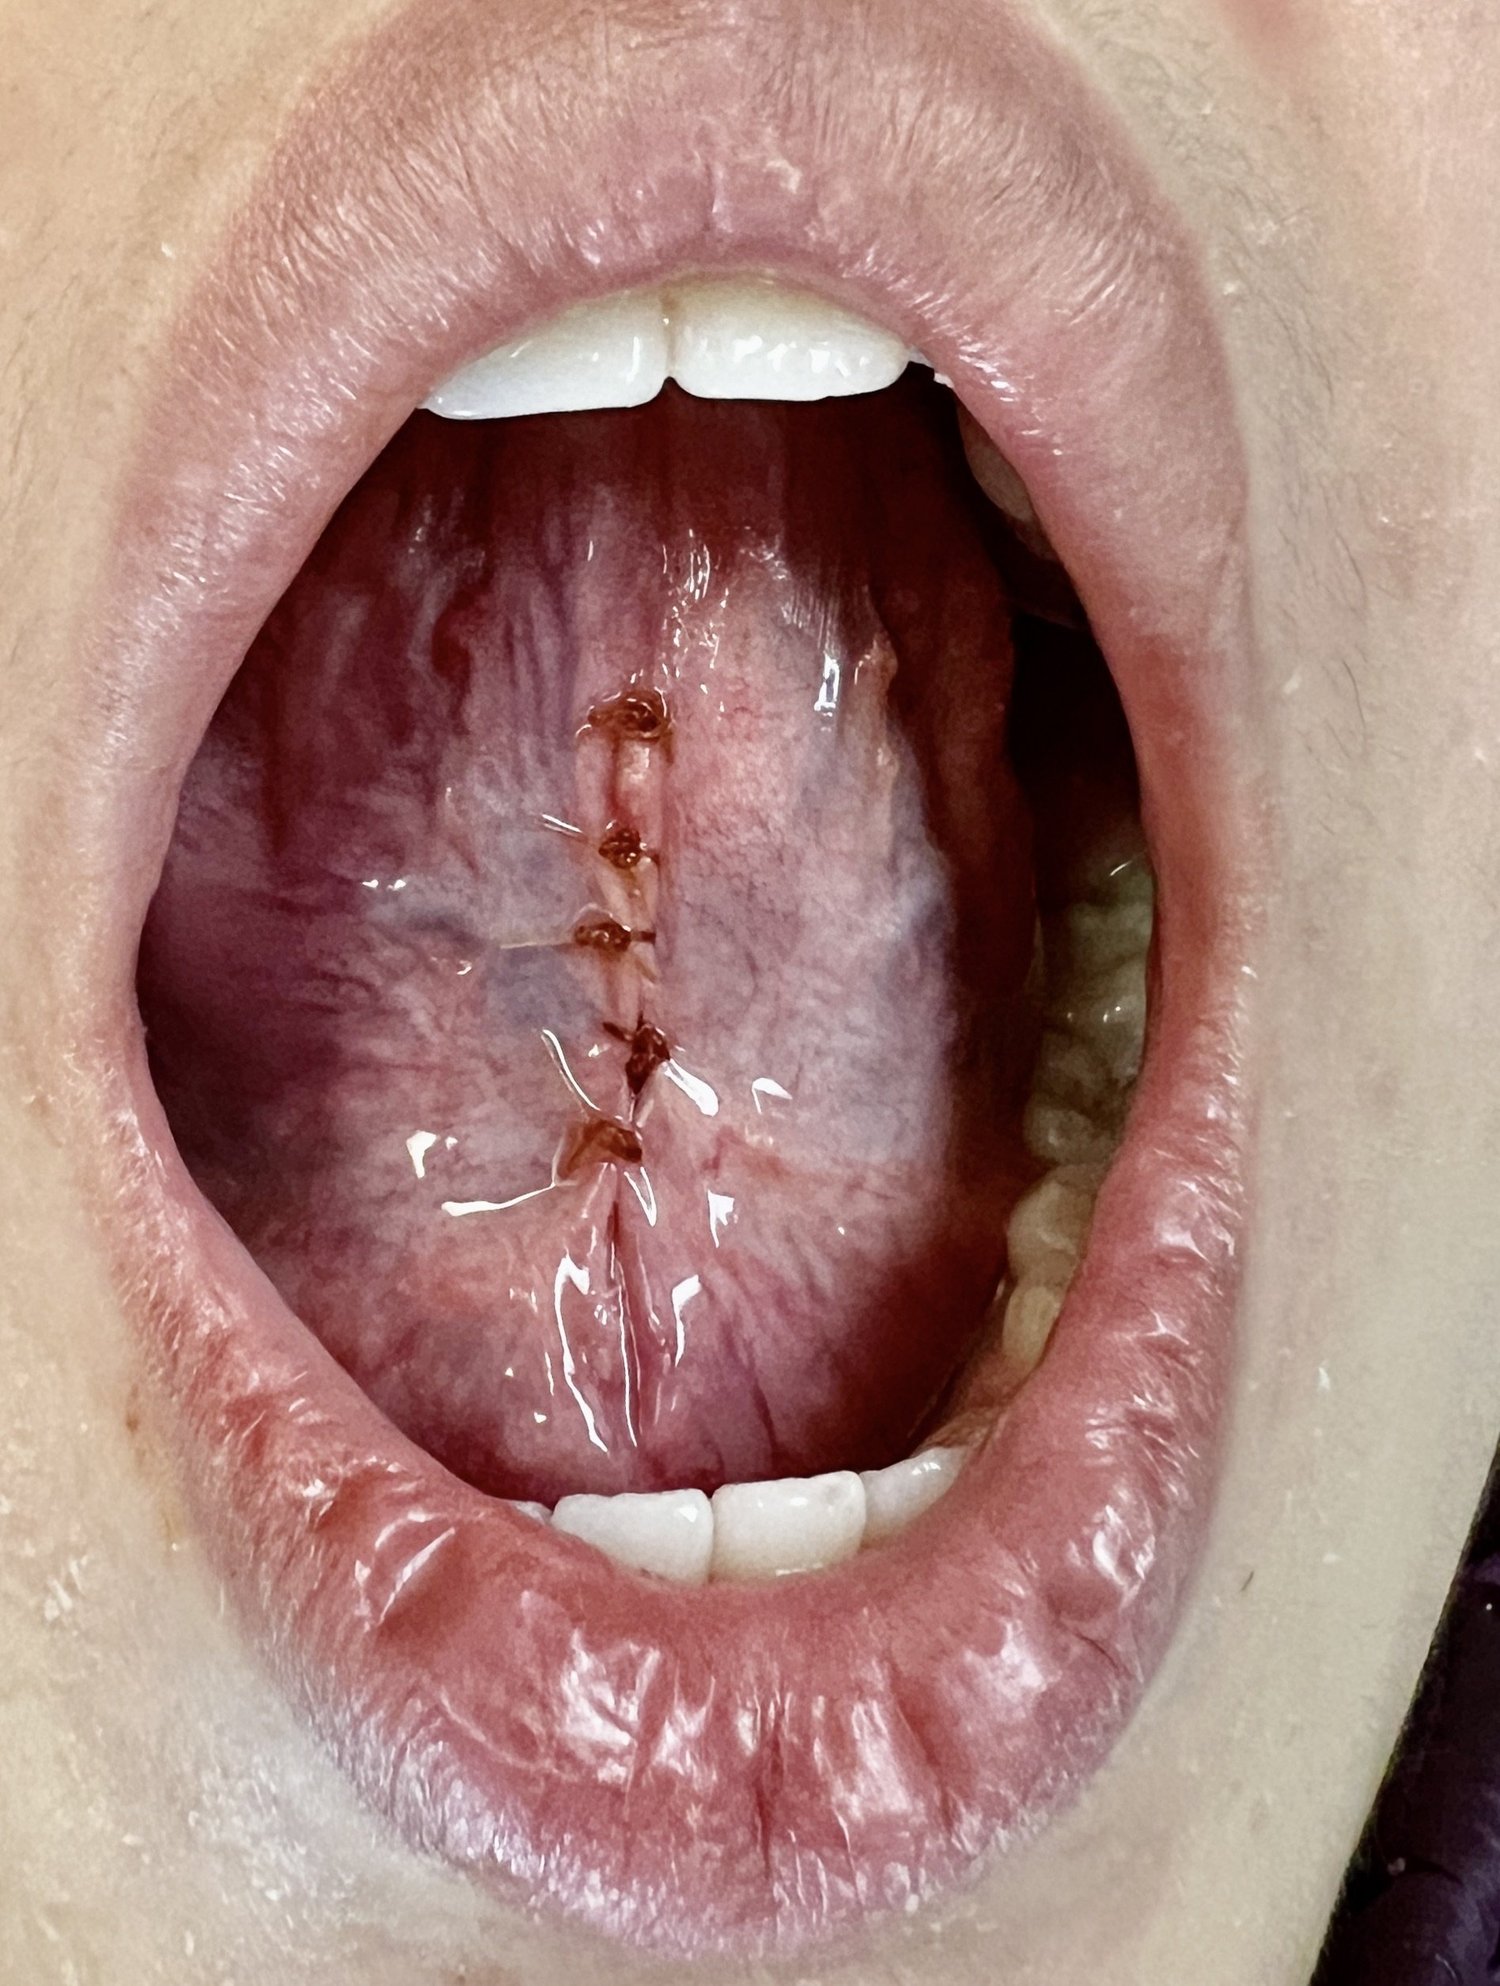

Tongue-Tie Release Using CO2 Laser Technology

Tongue-tie, also known as ankyloglossia, is a condition present at birth that restricts the tongue’s range of motion. With tongue-tie, an unusually short, thick, or tight band of tissue (lingual frenulum) tethers the bottom of the tongue’s tip to the floor of the mouth.

As the head moves forward in relation to the cervical spine, the increase in load is 10 lbs. for every inch forward displacement of the head. The treatment for a tongue-tie is a lingual frenectomy, wherein the tethered band of tissue is released using a CO2 laser along with the required myofunctional therapy.